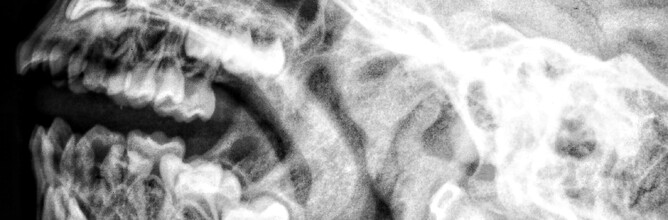

Temperomandibular Joint (TMJ) Dysfunction and Chiropractic approach of TMJ Treatment

TMJ dysfunction (Jaw dysfunction) is a commonly experienced musculoskeletal issue.  People regularly consult us for Chiropractic advice regarding TMJ issues, from clicking, soreness to Jaw tension that seems linked with headaches.  Chiropractic care is focusse...